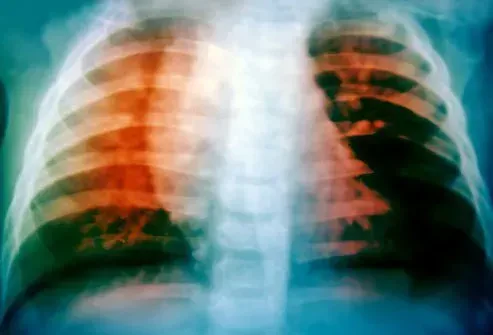

Tubercolosi (TB)

Ha ucciso lo scrittore George Orwell e il compositore Frederic Chopin. Molte persone pensano che sia scomparso dopo che sono stati sviluppati trattamenti efficaci. Ma la tubercolosi (TB) uccide ancora. In effetti è ancora una delle prime 10 cause di morte in tutto il mondo secondo l'OMS (Organizzazione mondiale della sanità). Le infezioni da tubercolosi sono ora limitate principalmente a 30 paesi con l'India e la Cina che rappresentano la maggior parte delle infezioni in generale. Mentre il trattamento è possibile, ci vogliono sei mesi in media e durante quel periodo la persona infetta rimane contagiosa. Tuttavia, i ceppi resistenti ai farmaci si sono sviluppati e il trattamento per questi possono richiedere due anni o più.